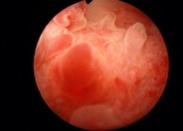

• 腺性膀胱炎

628健康網為您分享有關腺性膀胱炎的癥狀,腺性膀胱炎的治療方法,腺性膀胱炎的預防知識,腺性膀胱炎的癥狀圖片,腺性膀胱炎...